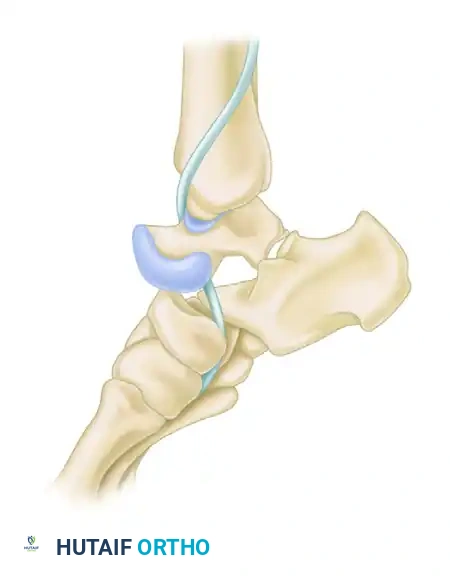

Irreducible Lateral Dislocations

Lateral subtalar dislocations frequently are irreducible by closed manipulation. The talar head is driven medially through the joint capsule, trapping medial structures.

* Offending Structures: The most common offending structures blocking reduction are the posterior tibial tendon (PTT) and osteochondral fractures of the talus or navicular. The PTT often wraps around the talar neck, creating a noose effect.

* Surgical Approach: These must be approached medially. An anteromedial incision is made centered over the prominent talar head.

Intraoperative view of an irreducible lateral dislocation. The posterior tibial tendon is acting as a physical obstacle to reduction, tightly bowstrung across the talar neck.

The posterior tibial tendon is identified and marked with a rubber band. It must be carefully mobilized and lifted over the talar head.

Successful reduction of the subtalar joint after removal of the interposed posterior tibial tendon and clearance of the fracture debris.